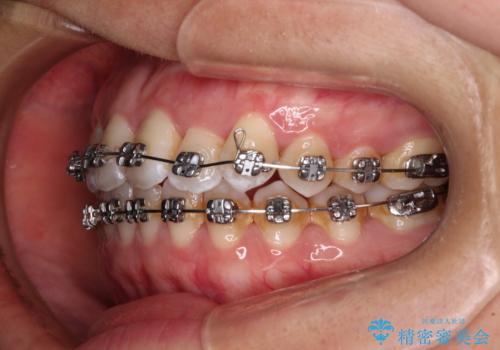

- 矯正装置

- メタルブラケット

上顎歯列および上顎骨が下顎に対して狭小であることが原因であるため、上顎の急速拡大装置を使用して上顎骨を側方に拡大することで反対咬合を改善し、ワイヤー装置で歯列を整えることとしました。